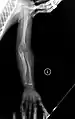

Having the same clinical features as Type IV, it is distinguished histologically by "mesh-like" bone appearance. Further characterized by the "V triad" consisting of (a) radio-opaque band adjacent to growth plates, (b) hypertrophic calluses at fracture sites, and (c) calcification of the radio-ulnar interosseous membrane.[24]

OI Type V leads to calcification of the membrane between the two forearm bones, making it difficult to turn the wrist. Another symptom is abnormally large amounts of repair tissue (hyperplasic callus) at the site of fractures. Other features of this condition include radial head dislocation, long bone bowing, and mixed hearing loss.